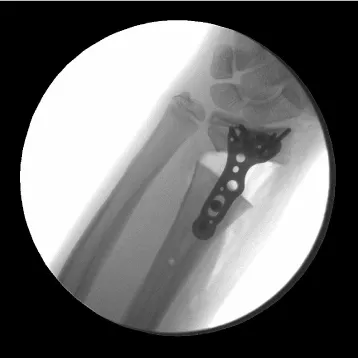

Three days after injury, consent was obtained, and the patient was taken to the operating room. There he underwent a manipulative closed reduction. Once reduction was obtained, percutaneous pin fixation was utilized to stabilize the fracture. Under flouroscopic guidance, two smooth 0.062 inch Kirschner wires were placed into the radial styloid tip and across the fracture site (Figure 2). Both pins were placed uneventfully with one attempted insertion. There were not multiple passes. The patient was then placed in a short arm cast that was split in the operating room.